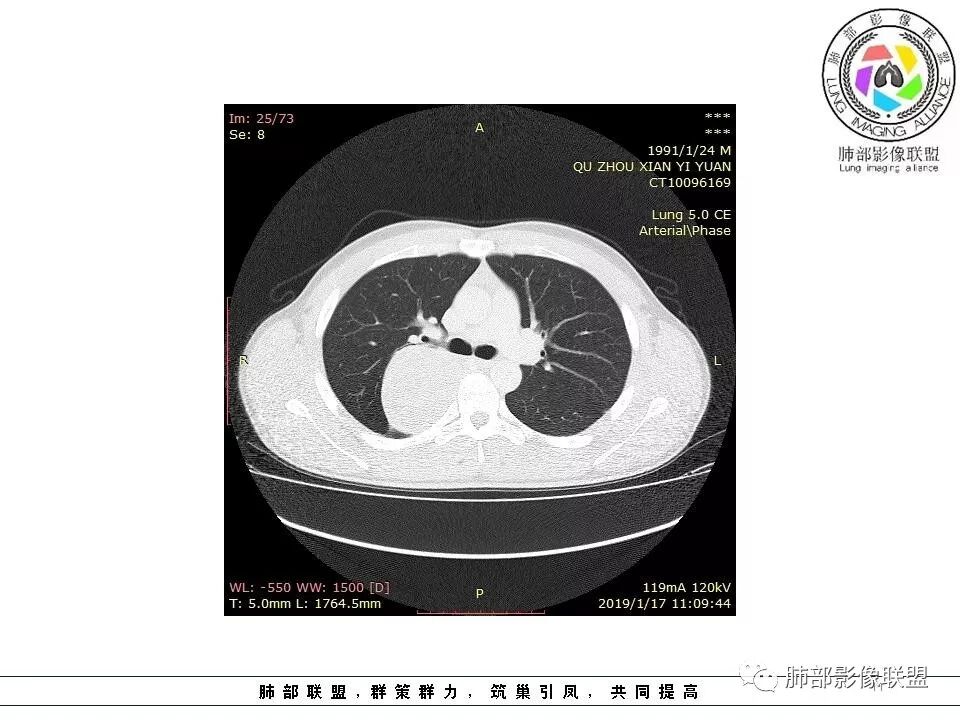

后纵隔脊柱旁占位性病变,疾病谱有神经鞘瘤,sft,节细胞瘤,髓外造血。此例有胸膜尾征,蛇纹征 ,延迟强化。考虑胸膜孤立性纤维瘤。看到有供血动脉,但不知道是哪里的血管。

后纵隔脊柱旁占位性病变,有胸膜尾征,胸膜下脂肪可见,蛇纹征,明显强化。考虑孤立性纤维瘤。

右侧后纵隔脊柱旁占位,边缘光滑清晰,内侧肺组织受压,外侧可见胸膜尾征,增强持续强化,并可见蛇纹血管征。考虑SFT

后纵隔脊柱旁占位性病变,有胸膜尾征,胸腔积液外推,蛇纹征,考虑孤立性纤维瘤。

青年男性,右侧后纵膈肿块,有胸膜尾征,支气管被推压,定位肺外,脏胸膜?血供来自肺动脉及肋间动脉,增强后有强化,蛇纹征,考虑SFT,鉴别鞘瘤

右肺占位,跨越上叶后段、下叶背,边缘光滑,瘤肺界面清,见肺压缩缘(线样不张`强化),见胸膜尾征,胸膜下脂肪未见明显增厚,肋骨丶脊柱未见侵袭及受压,渐进性丶地图样强化,冠状位似见体循环供血

诊断:SFT(来源壁层胸膜?一般小于20%)

右侧后纵膈肿块,有胸膜尾征,周围肺组织及支气管被推压,定位肺外,脏层胸膜来源,血供来自肺动脉或者支气管动脉,增强后持续渐进强化,蛇纹征,考虑SFT,鉴别鞘瘤。

青年男性,右后上纵隔脊柱旁沟可见团状软组织影,边界清,密度尚均匀,推挤邻近肺组织,胸膜可见掀起,有肺动脉供血,增强轻度蛇皮样强化,纵隔淋巴结未见肿大,邻近骨质未见破坏,胸膜下脂肪间隙消失,考虑SFT孤立性纤维瘤可能性大,鉴别神经鞘瘤,节细胞瘤,建议活检。

右肺上叶纵膈胸膜侧一类圆型肿块,宽基地与胸膜相连,呈D征,边缘光滑,肺部支气管及血管推移,平扫密度均匀,增强后轻度渐近性强化,并可见肋间动脉供血,病变与食管关系模糊,考虑肺外来源,孤立性纤维瘤(有血管穿行),鉴别神经鞘瘤(强化弱,而且椎孔未见扩大),淋巴瘤

右上胸腔脊柱旁类圆形肿块影,呈D字,有胸膜尾征,肺瘤界面清楚,密度欠均匀,增强蛇纹征,渐进性强化,考虑孤立性纤维瘤,鉴别神经源性肿瘤。

右后纵膈肿块,肺瘤界面清楚,胸膜尾征,邻近肺组织及支气管被推移,部分脂肪间隙存在,定位肺外来源,血供来自肋间动脉,增强后持续渐进强化,蛇纹征,考虑SFT,鞘瘤肿块内血管罕见,不考虑。

右上肺野脊柱旁软组织肿块,边缘光滑整齐,肺组织及气管右肺上叶支气管受压前移,外移,边缘可见胸膜尾征,病灶内密度不均,增强后渐进性持续强化,其内可见明显蛇纹血管征,首先考虑肺外来源,sft.可能性大

青年男性,右侧脊柱旁占位,瘤肺界限清晰,支气管推移,胸膜尾,D字征,胸膜下脂肪影,蛇纹血管,双重供血,延迟强化,定位胸膜,支持sft

病灶边缘清爽,内见蛇形血管影有特征   D字形与胸膜紧贴

右侧脊柱旁肿块,边界清晰,密度稍欠均匀,宽基底与胸膜相贴,脂肪间隙消失,见胸膜尾征,增强有强化,见蛇纹血管,定位胸膜,考虑SFT(孤立性纤维瘤)。

青年男性,瘤肺边界锐利,气管向前推移,定位肺外,局部胸膜增厚,后方见少量积液,提示脏层胸膜来源,增强持续渐渐进性强化,内见蛇纹血管,考虑sft

后纵隔脊柱旁占位性病变,有胸膜尾征,蛇纹征,考虑孤立性纤维瘤。

应该是来自脏壁胸膜,有尾征,蛇纹征,SFT

右侧脊柱旁肿块,边界清晰,密度尚均匀,宽基底,后方见胸腔积液,定位于肺外。增强后不均匀强化,考虑sft。鉴别神经源性肿瘤。

边缘光滑,宽基底与胸壁相连,跨叶裂,叶裂稍前推,血管、支气管前移。

浅分叶

外上侧少量胸水

肋间动脉供血,强化尚均匀,逐步强化

1.右上胸内脊柱旁类圆形肿块,质地似乎比较坚实,密度稍显不均,但未显示明确的坏死。

如此密度形态的病灶位于肺边缘首先应当想到孤立性纤维瘤,可相邻胸膜未见明显的异常强化和胸膜方向延伸。

注意所谓“胸膜尾征”的概念及形成机制与“脑膜尾征”是大不相同的。